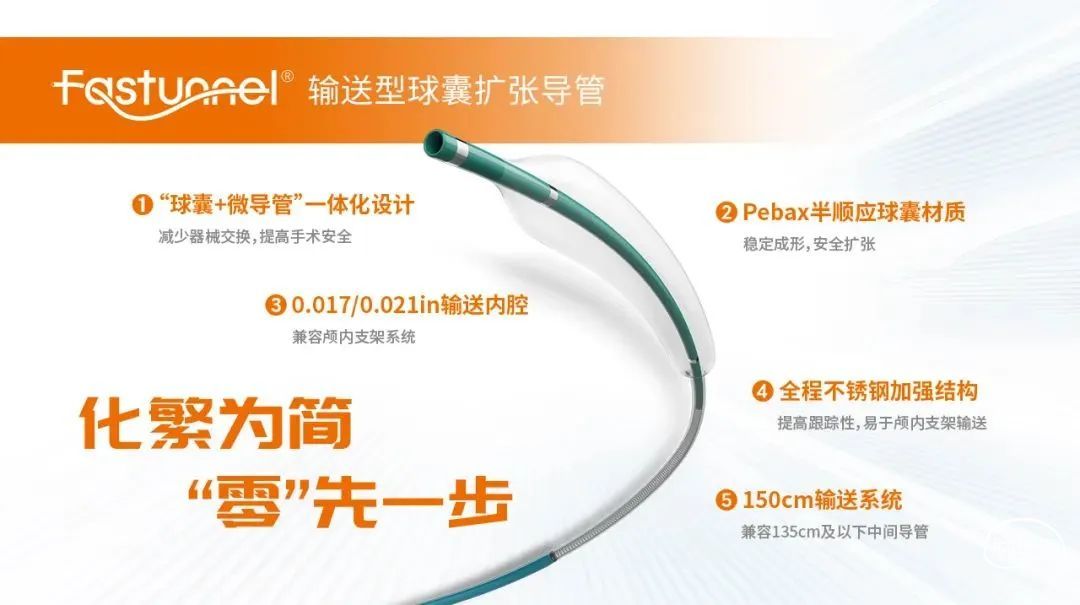

近期,云南省建水县人民医院胡亚教授团队成功应用Fastunnel®输送型球囊扩张导管(下文简称“Fastunnel®”)完成一例左侧大脑中动脉M2段重度狭窄介入治疗手术,治疗结果得到临床认可!

器械准备

0.014inch 微导丝

150cm*11cm 微导管

6F 125 颅内支撑导管

21系列 Fastunnel®输送型球囊扩张导管 2.0mm*10mm

4.5mm*22mm 自膨式闭环支架

加奇生物Fastunnel®输送型球囊扩张导管是“球囊+微导管”一体化设计,减少了器械交换,提高了手术安全。材质是Pebax半顺应球囊,稳定成形,安全扩张。还具有全程是不锈钢加强结构,提高跟踪性,易于颅内支架输送。